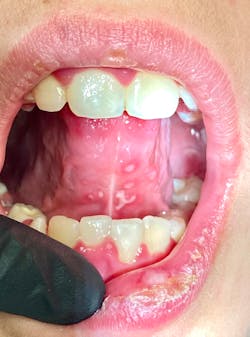

Note: The pictures are not of the highest quality as the patient was in extreme discomfort when I took them.

Differential considerations include:

Definitive diagnosis is likely one of two: Herpangina or acute primary herpetic gingivostomatitis

The saying “nothing is for certain unless it’s in a petri dish” stands true in all pathology cases, including this one. However, based on the symptoms and clinical presentation, I was able to surmise that it was more than likely either herpangina or APHG, although I’m leaning toward APHG.